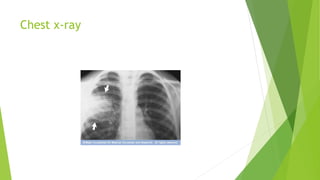

Chest x-ray

โ€ขChest X-ray.

โ€ขThis helps your doctor diagnose pneumonia and determine the extent

and location of the infection.

โ€ขHowever, it can't tell your doctor what kind of germ is causing the

pneumonia.